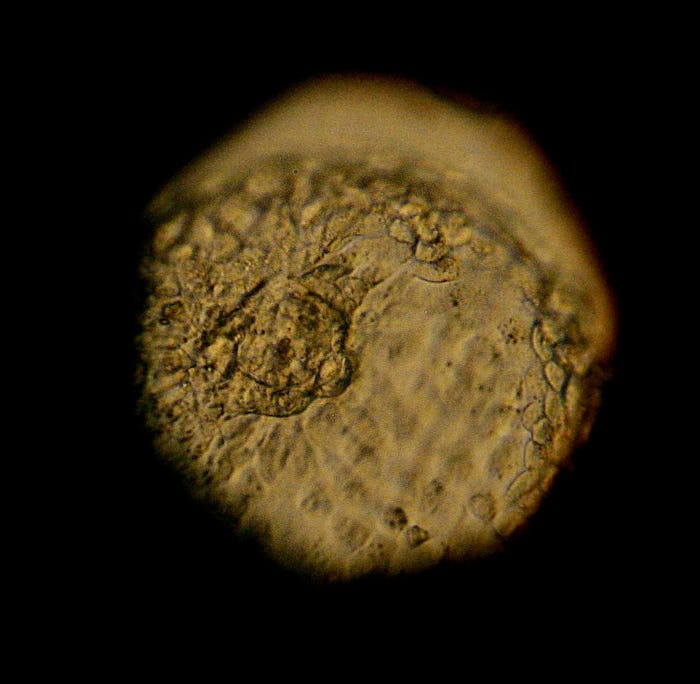

For years, women looking to conceive have been able to track their ovulation cycles to know when is the best, most fertile time to try to get pregnant. Now, for couples thinking about using the in vitro fertilization, or IVF, method there’s reportedly a new calculator that may help predict the best time for a successful IVF treatment before they undergo the costly infertility procedure, a new study claims. The new findings may be able to alleviate the burden of guessing, as the predictability factor traditionally could not be assessed until after a couple completed at least one round of IVF — a technique that allows doctors to assess the quality of sperm and eggs if the first round proves to be unsuccessful.